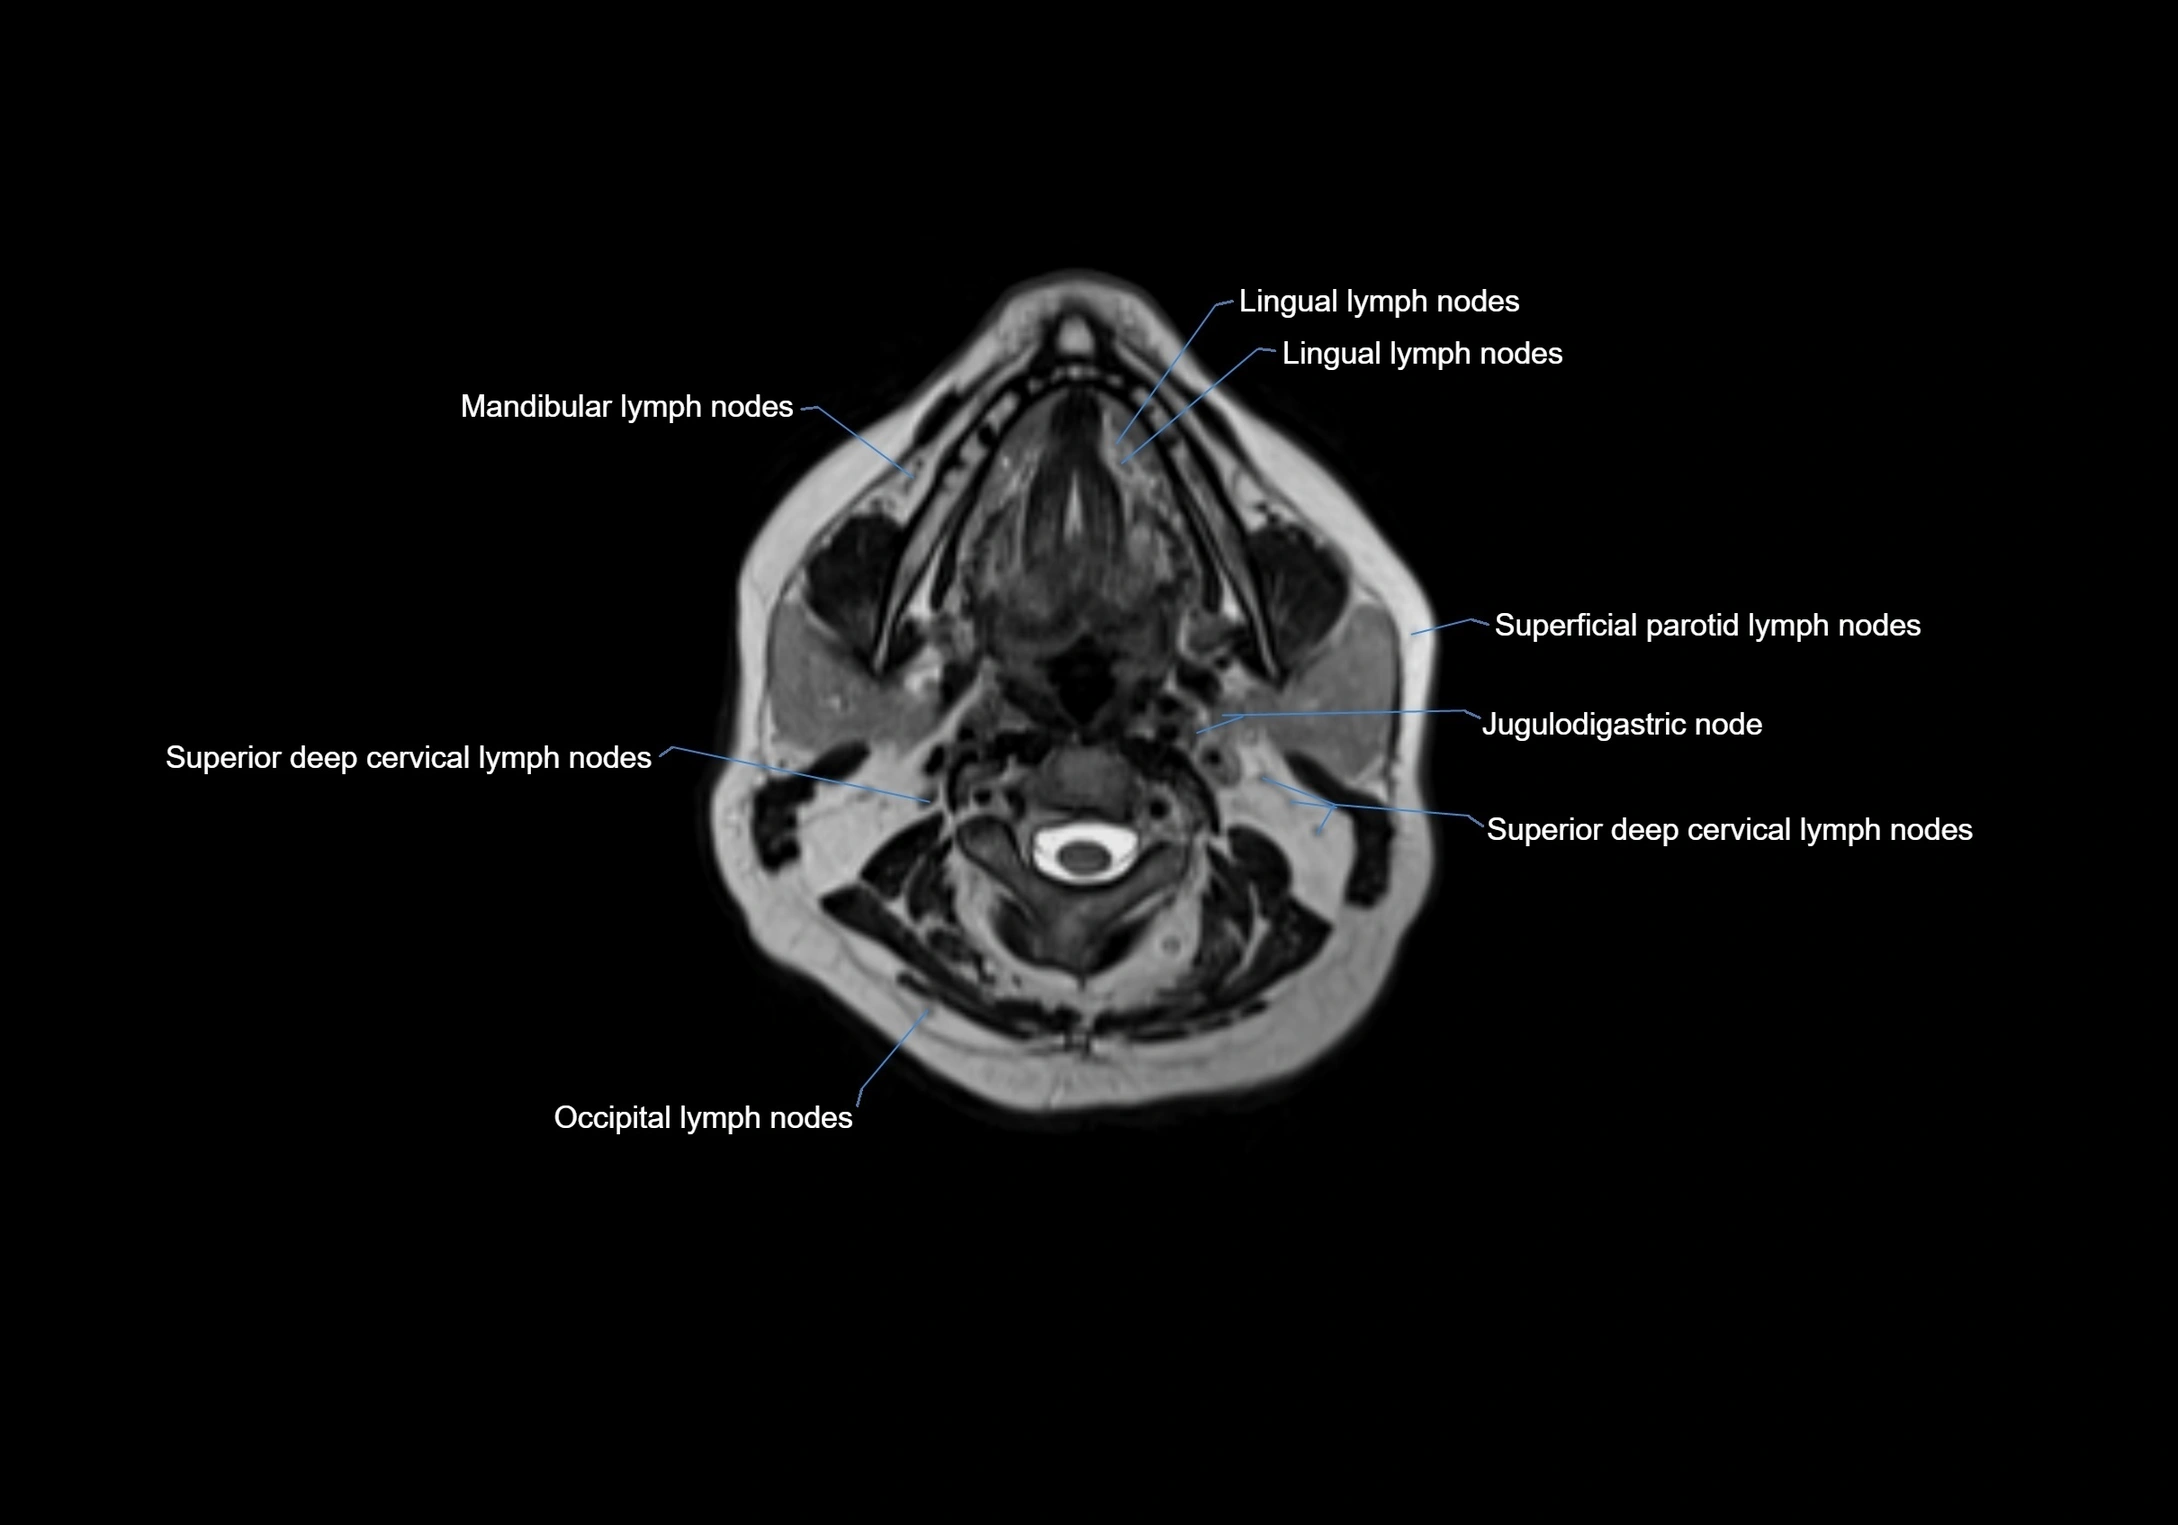

Accessory lymph nodes are small, secondary lymph nodes located along the main facial and cervical lymphatic chains, often adjacent to primary lymph nodes, such as preauricular, submandibular, or occipital nodes. They are typically less than 5 mm in diameter, embedded within subcutaneous fat or connective tissue, and may be variable in number and location. These nodes provide additional filtration and immune surveillance for lymph collected from the face, scalp, and neck regions. Accessory lymph nodes are usually non-palpable in healthy individuals but may enlarge in response to infection, inflammation, or metastasis, making them clinically significant.

• Found along primary lymph node chains, including preauricular, submandibular, parotid, and occipital regions

• Embedded in subcutaneous fat or superficial fascia, often lateral or posterior to primary nodes

• Variable in number; may occur unilaterally or bilaterally, depending on individual anatomy